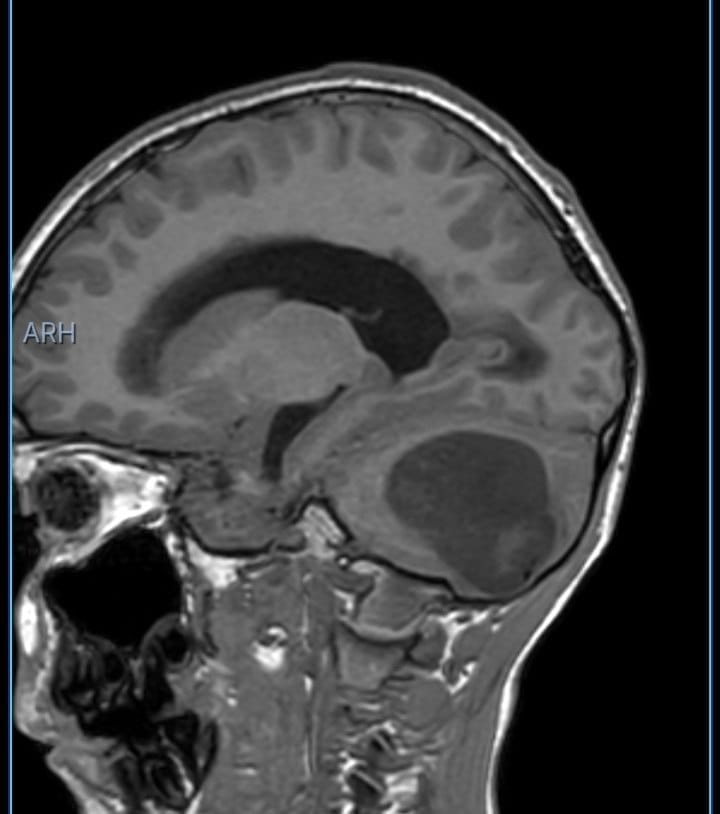

Sebasthian González, un niño de 10 años oriundo de la Isla de Margarita, fue diagnosticado con un quiste aracnoideo ubicado en la parte posterior de su cerebro que requiere una intervención quirúrgica urgente cuyo costo asciende a 21.000 dólares.

De acuerdo a sus familiares, González comenzó a presentar dolores de cabeza intensos, vómitos persistentes por las mañanas y un empeoramiento progresivo de su estado neurológico. Tras una evaluación médica, los especialistas encontraron el tumor en su cabeza, el cual le está provocando una hidrocefalia obstructiva y una hipertensión endocraneana severa.

El reporte del Hospital Clínicas del Este detalló que el menor de edad necesita de una hospitalización inmediata y la colocación de un sistema de derivación ventriculoperitoneal para aliviar la presión en su cerebro, seguido de una segunda intervención quirúrgica para tratar y extirpar la lesión.